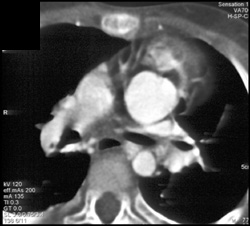

Diseased Aortic Valves